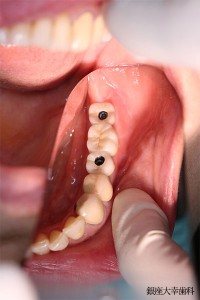

②

(ミラー面観)

↑UCLAブリッジが入ったところです。(アクセスホール)ネジ穴は開いたままの状態です。